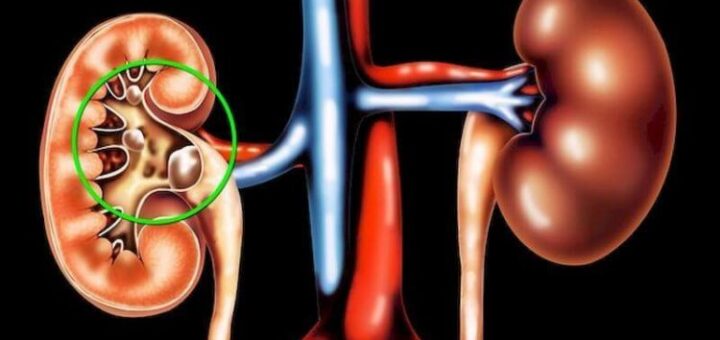

Камені в нирках: продукти, які провокують їх появу